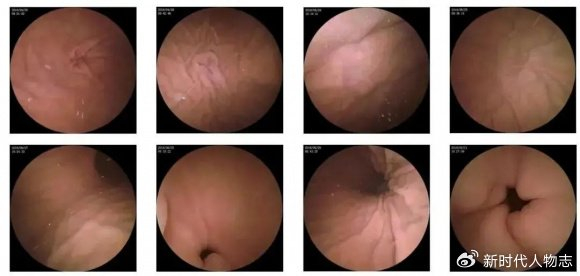

肛門息肉早期圖片及其相關介紹,肛門息肉早期圖片與詳細介紹

摘要:本文介紹了肛門息肉早期的圖片和相關介紹。肛門息肉是肛門部位的一種常見病變,早期發現對于治療具有重要意義。文章通過圖片展示了肛門息肉的早期形態,并簡要介紹了其癥狀、原因、診斷和治療等方面的信息,以幫助人們更好地了...